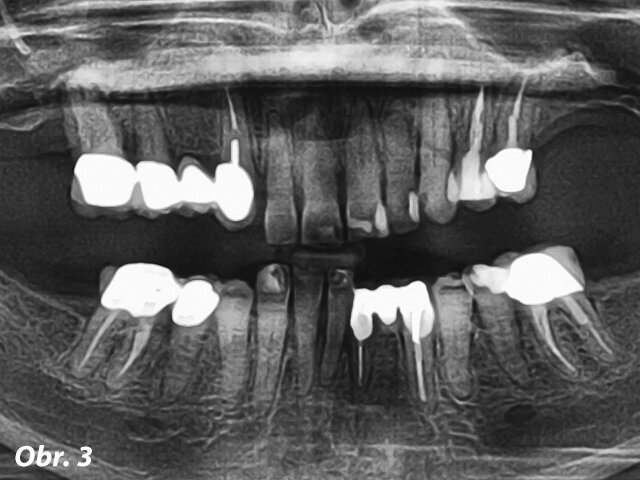

Parodontolog a kolega z ITI, jejichž praxe je dvě hodiny od té naší, doporučili našemu týmu tuto pacientku. Nejdříve byla vyšetřena protetikem dr. Harrym Randelem a následně parodontologem dr. Robertem Levinem pro zajištění týmového přístupu k řešení jejího selhávajícího chrupu. Pacientka se dostavila do naší ordinace jako 65letá nekuřačka (ASA 3: kompenzované nemoci: úzkost/deprese, osteoathritida, fibromyalgie, hypothyreóza a v minulosti myofaciální bolestivá dysfunkce, obr. 1–3). V minulosti si prošla problémy s TMK (např. lupání a bolest v pravém TM kloubu), které jsou v současnosti pod kontrolou a nebolestivé.

Hlavním požadavkem pacientky bylo vylepšení svého estetického vzhledu a komfortu s přáním permanentního a rychlého řešení jejího selhávajícího chrupu. Ve finálním ošetření si rovněž přála redukci gummy smile ve frontální části maxily. Dostavila se do naší ordinace ke třetí chirurgické konzultaci ohledně imediátního zatížení maxilární a mandibulární hybridní rekonstrukce prostřednictvím terapeutického konceptu Straumann® Pro Arch (šikmé zavedení distálních implantátů umožní vyhnout se anatomickým strukturám jako sinus maxillaris, foramina mentalia mandibulae). Tento terapeutický koncept zredukoval potřebu komplementárních chirurgických zákroků a množství implantátů potřebných pro zhotovení fixní hybridní rekonstrukce v rozsahu prvních molárů. Při širokém úsměvu byla zaznamenána střední až vysoká retní linie s dvojúrovňovou okluzní rovinou. Rovněž byla registrována supraokluze horních a dolních frontálních zubů (FDI: 12, 11, 21, 22 a 41–43, US: 7–10 a 25 až 27) vytvářející hluboký skus 6 mm (obr. 2). Ve vzájemném vztahu špičáků byla zaznamenána I. An-

gelova třída s předkusem 6 mm a překusem 6 mm. Vzhledem k hyposalivaci související s její medikací byly pozorovatelné generalizované rekurentní kazy. Hloubka sondáže parodontu se pohybovala od 4 do 7 mm v horní čelisti a od 4 do 6 mm v čelisti dolní s mírným až těžkým krvácením marginální gingivy v obou čelistech. U zubu 6 (FDI: 13) byla klinicky zjištěna vertikální fraktura. Zuby horní čelisti vykazovaly silnou viklavost pohybující se mezi 2.–3. stupněm: 3, 7–13, 20–26 a 29 (FDI: 16, 12, 11, 21 až 25, 31–35, 41–42 a 45). Její profilování z hlediska compliace se svým předchozím zubním lékařem bylo dobré, avšak udávala, že vždy mívala „problémy se svými dásněmi.“

Předběžný terapeutický plán diskutovaný při iniciální návštěvě s pacientkou a jejím manželem zahrnoval následnou diagnózu: generalizovaná mírná až pokročilá parodontitida; generalizované rekurentní kazy vztahující se k suchosti v ústech související s její medikací; zkrácené zubní oblouky s poruchou vertikálního rozměru okluze („mutilovaný chrup“). Prognóza: všechny přítomné zuby nemají naději na záchranu.